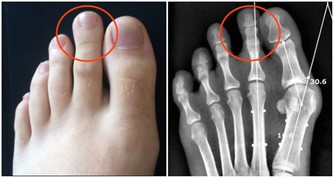

1.“老痔瘡”竟是腸癌

據了解,30%的腸癌初期都被誤以為是痔瘡,因為腸癌與痔瘡症狀十分相似,出現病變位置也相似,且都有便血。大部分人群一旦發現便血簡單地以為痔瘡老毛病又犯了,並不加以重視。

辨析要點:腸癌多為暗紅色、帶粘液的便血,伴隨大便形狀與習慣的改變;而痔瘡便血多為鮮紅色滴血,通常無大便形狀的改變,頂多便秘。肛門指檢與腸鏡能快速診斷兩者。